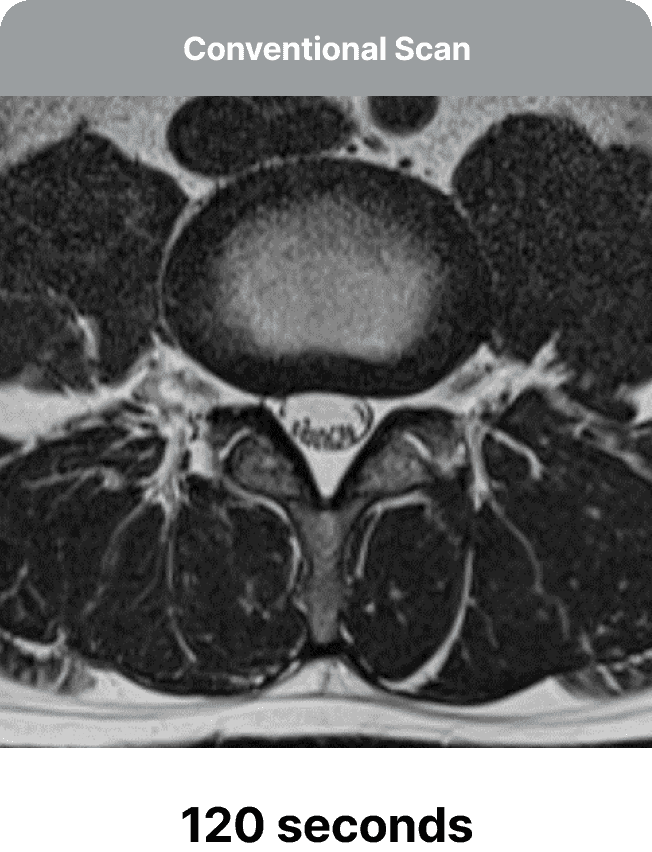

Our team will optimize MRI protocols to accelerate scans, initially producing faster yet low-quality images. SwiftMR's deep learning model is then employed to enhance the accelerated scans, effectively transforming them into high-quality images.